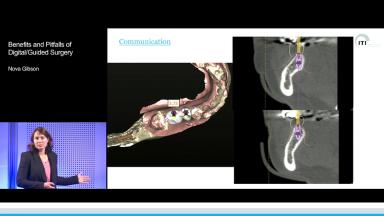

Benefits and Pitfalls of Digital/Guided Surgery

Digital or computer-guided surgery has been widely used in maxillofacial surgery with great enthusiasm. There is substantial benefit to digital planning and surgical guide usage in mandibular reconstructions with fibula grafts. Benefits of guided surgery are presented through multiple case presentations during this lecture. Digital surgical guides include both mandibular resection guides, fibula harvesting guides, and customized milled titanium plates for mandibular fixation. Surgical guides are improving the accuracy of such complex operations, as precise bone-to-bone contact is crucial to the success of these surgical procedures. They substantially influence the efficiency of the surgical procedure and shorten the time needed to perform complex surgical treatments, which often involve two surgical teams.

- recognize the benefits of computer-guided technology in complex surgical reconstructions

- discuss the indications for computer-guided flapless surgical procedures